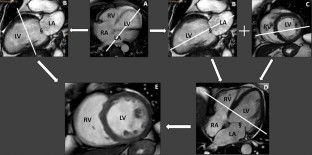

Fig. 1